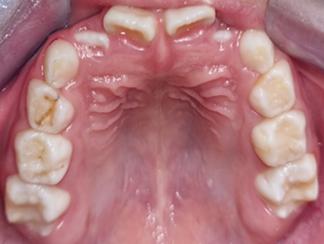

1. Carpio-Deheza G. Manual de instrucciones para la presentación de protocolos y monografías de diplomados, protocolos y tesis de espcialidad clínica/ quirúrgica, tesis de maestrías y doctorados en salud. Cochabamba: Universidad Mayor de San Simon, Facultad de Medicina Dr. Aurelio Melean, post grado UMSS; 2019.

2. Patrias K. Citing Medicine; The NLM Style Guide for Authors, Editors, and Publishers. [Online].: Bethesda (MD): National Library of Medicine (US); 2007 [cited 2022 marzo 29. Available from: https://www.ncbi.nlm.nih.gov/books/NBK7256/.